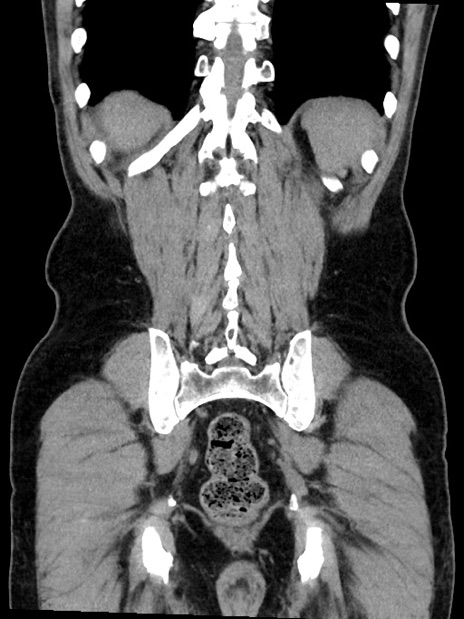

症例35(冠状断像)

【症例】70歳代 男性

【主訴】腹部膨満、嘔吐

【現病歴】昨日より腹部膨満感出現。本日増悪し、仙痛出現。嘔吐あり、受診。

【既往歴】糖尿病、胆摘後

【身体所見】BP 149/80mmHg、HR 74/min、BT 35.9℃、腹部:膨満、軟、圧痛なし。腸雑音減弱あり。上腹部正中切開瘢痕あり。

【データ】WBC 13500、CRP 1.72